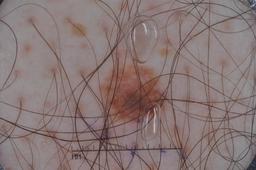

Evaluation set from the ML challenge: SIIM-ISIC Melanoma Classification.